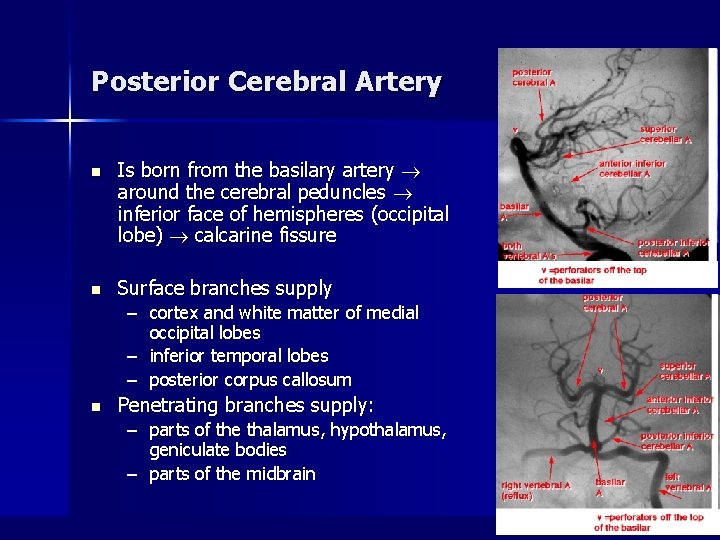

Posterior Cerebral Artery n Is born from the basilary artery around the cerebral peduncles inferior face of hemispheres (occipital lobe) calcarine fissure n Surface branches supply – cortex and white matter of medial occipital lobes – inferior temporal lobes – posterior corpus callosum n Penetrating branches supply: – parts of the thalamus, hypothalamus, geniculate bodies – parts of the midbrain